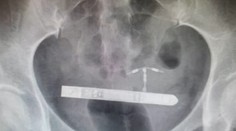

Pár si chcel spestriť romantické chvíle. Skončilo sa to bolestivými vibráciami v bruchu a operáciou Róbert Ďurkáč 28. 1. 2020